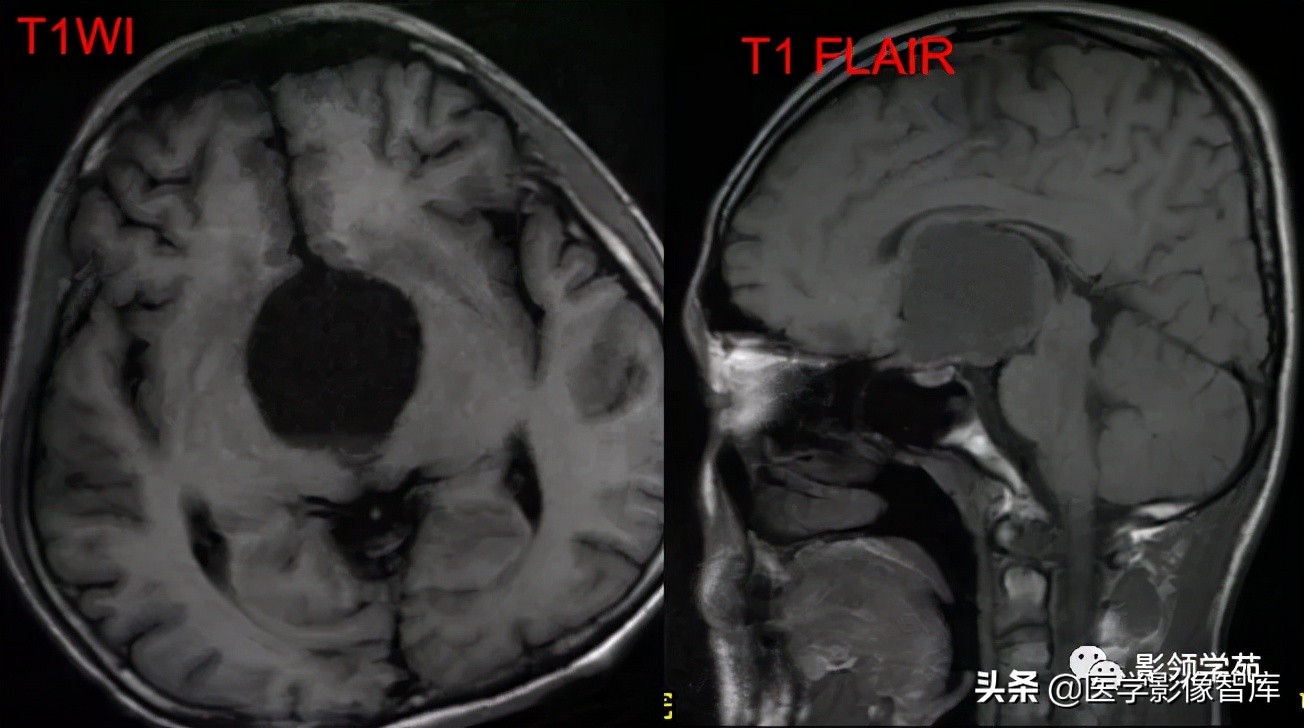

鞍区占位肿块,呈等T1等T2信号,信号均匀,边界清楚。

病灶呈均匀、显著强化(馒头样),以宽基底与前颅窝底相连,

冠状位和矢状位见脑(硬)膜尾征;

肿块突入鞍上池,向上推压视交叉,后缘紧邻垂体柄,与双侧颈内动脉相邻。